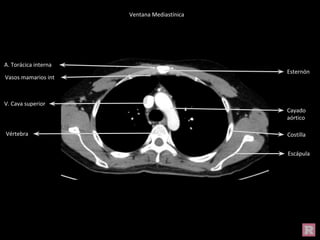

Cayado aórtico

V. Cava superior

Costilla

Escápula

Esternón

Vértebra

A. Torácica interna

Vasos mamarios int

Ventana Mediastínica

Cayado

aórtico